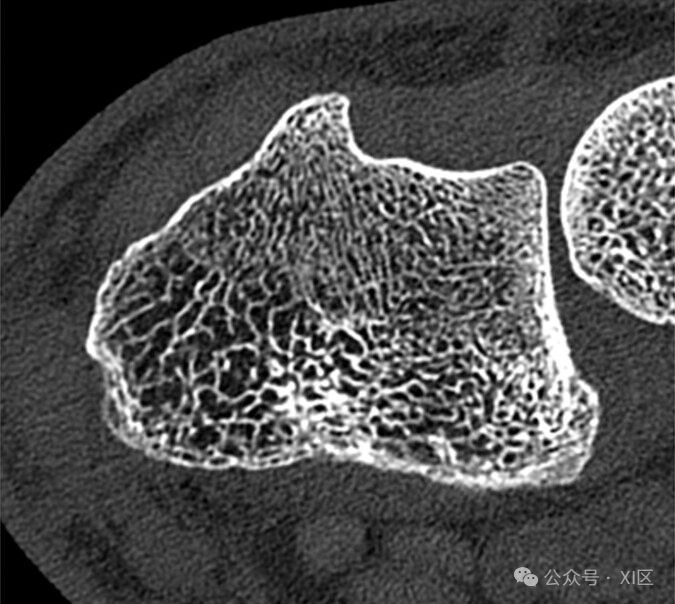

26岁男性,舟骨骨折患者。图像显示腕部在利斯特结节水平(窗宽,1500 HU;窗位,450 HU)。轴位超高分辨率(UHR)能量积分探测器CT图像显示,与下图相比,单个小梁的分辨率较低。该检查使用SOMATOM Force扫描仪(西门子医疗)在120 kV下进行,CTDIvol为14.4 mGy。图像以0.4毫米层厚、卷积核Ur73和512 × 512矩阵大小重建。

光子计数探测器CT图像显示出比上图更高的分辨率的单个小梁(即使两个扫描都是使用UHR模式获得),这是因为减少了部分容积效应和更高的空间分辨率。该检查使用SOMATOM Count Plus扫描仪(西门子医疗)在120 kV下进行,CTDIvol为9.7 mGy。图像以0.4毫米的截面厚度用Br84核和1024 × 1024矩阵大小重建。